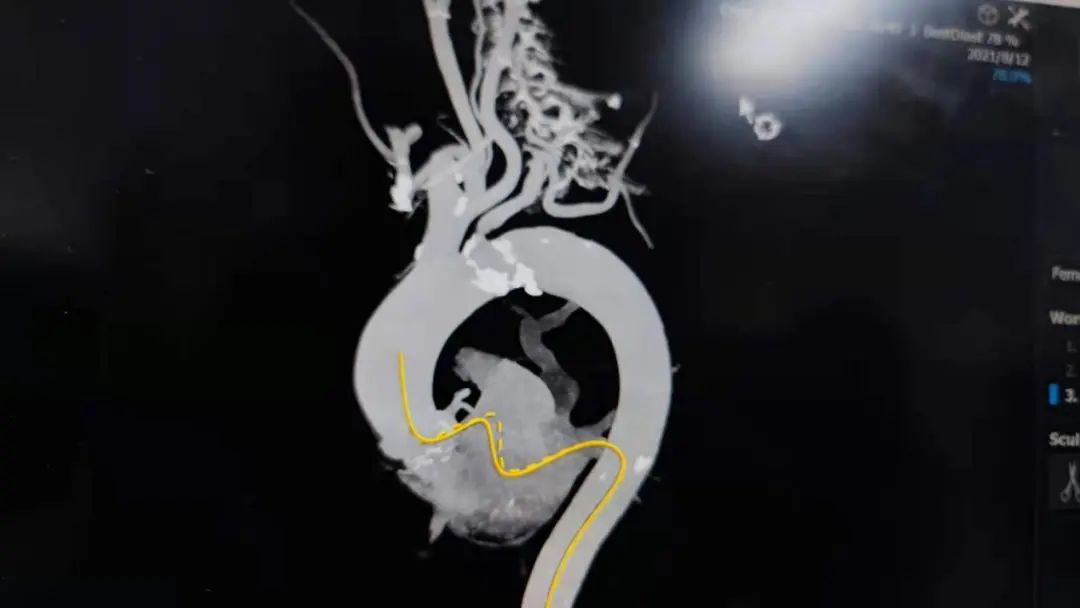

患者主动脉瓣呈三叶瓣,轻度钙化,法式窦结构不大,双冠高度可,升主动脉未见明显增宽,心脏角度约55°,左室小,心肌肥厚,主动脉弓部走行较平缓,但有明显钙化斑块,考虑到术中斑块脱落导致的卒中的风险,选择颈内动脉先行植入Emboshield Nav6抗栓塞远端保护装置进行保护,再行TAVR术。

彭小平教授团队组织各兄弟科室集体对其病变进行深入分析、反复讨论后,结合患者主动脉根部情况及病情等综合因素,决定使用VenusA-Plus®可回收输送系统,选用18 mm球囊预扩张,经由右侧股动脉入路拟植入L23型号瓣膜完成此次手术。

选用18mm球囊进行预扩张,通过造影观察,主动脉瓣重度狭窄,预期病人耐受球囊扩张后的反流。考虑瓣环20.2mm的直径、左室流出道19.9mm的直径、钙化分布等因素,因此判断瓣环结构对瓣膜位置要求极高,有较高风险发生瓣周漏,通过FEops技术进行综合评估后,考虑选用L23型号瓣膜,并采取标准位释放。